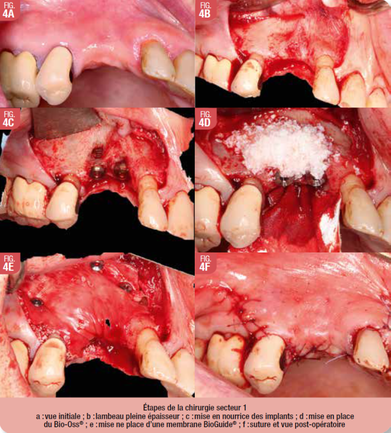

Préparation secteur 1

Les étapes de l’intervention de l’aménagement osseux et la pose des implants en place de 14-15 sont (Fig. 4), anesthésie locale avec articaïne adrénalinée à 1/100000eme, désinfection endo et exo-buccale à la bétadine et champage stérile, incision sur crète avec décharges mésiales et distales, Lambeau de pleine épaisseur, Pose de deux implants TSV Zimmer® torque à 35N avec vis de couverture, aménagement en épaisseur par apposition de matériaux de substitution osseuse xénogénique (Bio-oss®) stabilisé par une membrane collagénique (BioGuide®) maintenue sur l’os en palatin et vestibulaire avec des pins, fermeture hermétique du site avec suture en monocryl 5.0, hémostase et conseils post-opératoires (Fig. 4).

Les implants présentaient une bonne stabilité primaire à la fin de l’intervention. Le saignement lors de l’intervention était normal. La patiente est revue à 15j. post-opératoire pour contrôle et la dépose des points. La cicatrisation est normale.